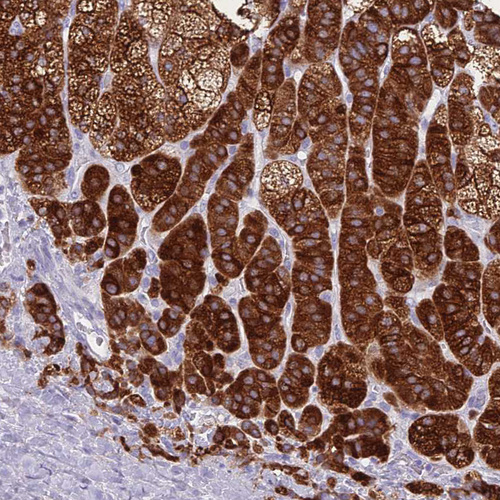

Immunohistochemistry analysis in human adrenal gland and kidney tissues using HPA048979 antibody. Corresponding CYP21A2 RNA-seq data are presented for the same tissues.